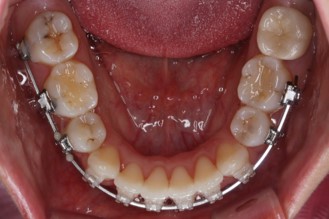

입안 모습입니다.

윗니와 아랫니 모두 각각 보면 가지런해 보이며 발치를 했던 자리도 거의 다 메워져서 양호해 보입니다. 훑어 보면 굳이 더 교정을 해야할 부분이 있을까? 싶겠지만 다음 사진을 보면 알 수 있습니다.

아랫니 모습입니다.

남아있는 발치의 공간이 없어졌으며 큰 이동이 없이 마무리가 되었습니다. 안쪽에는 발치공간이 다시 벌어지지 않도록 유지철사를 길게 연장해서 붙였습니다.